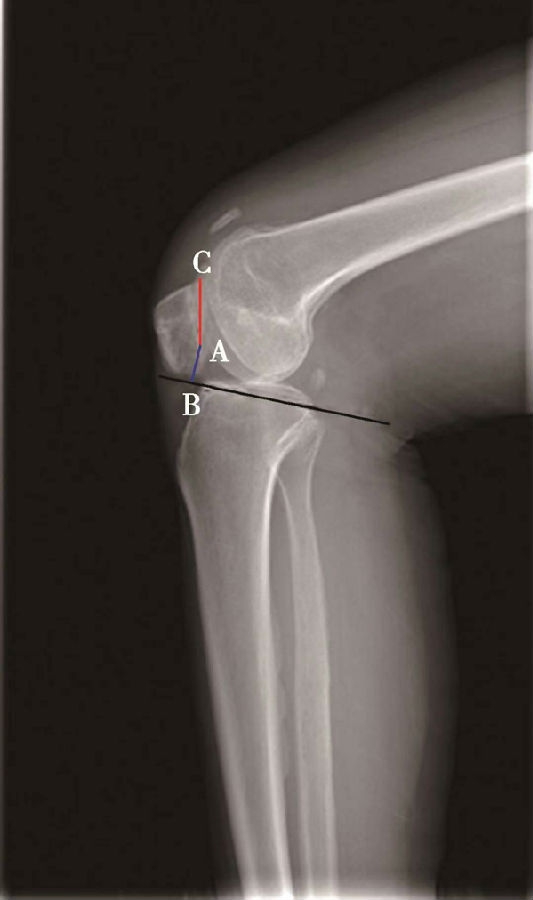

体位:侧卧位,屈膝无要求。

如图示:AB是髌骨关节面最低点到胫骨平台延长线的垂直距离。AC是髌骨关节面的长度。BlackBurne-Peel指数=AB/AC(图7)。

该方法同样可以评估胫骨结节移位或胫骨高位截骨术后的髌骨高度。但是也有其缺点:①部分患者的髌骨形态异常,难以分辨髌骨关节面的长度;②标记胫骨平台的延长线也需要较高的精度;③胫骨平台后倾角越大,可能导致髌骨关节面的最低点到胫骨平台的延长线的垂直距离越短。因此,如果手术改变了胫骨平台的后倾角度,则会使BlackBurne-Peel指数出现偏差。

图7 BlackBurne-Peel指数=AB/AC=0.80,为正常髌骨高度

图8 BlackBurne-Peel指数=AB/AC=1.20,为高位髌骨

图9 BlackBurne-Peel指数=AB/AC=0.49,为低位髌骨